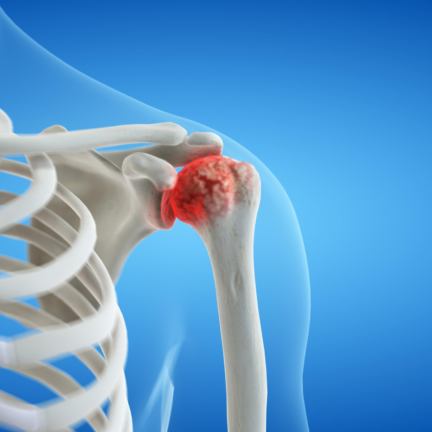

Shoulder Arthritis